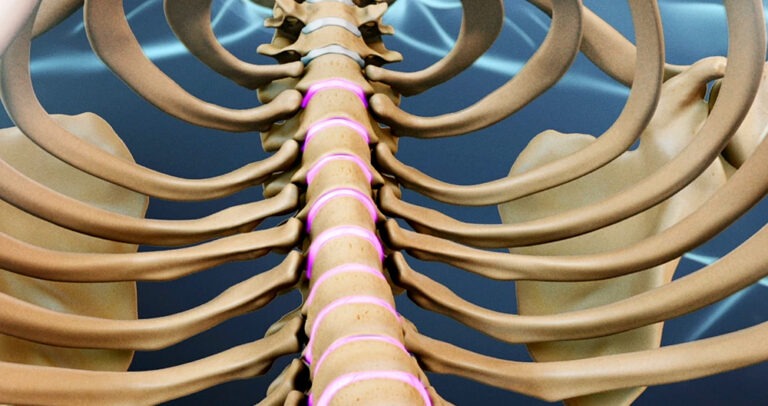

When a thoracic disc herniates, the spinal cord can be damaged. The spinal canal in the thoracic spine’s narrowest part is very dangerous. Anything that takes up space within the canal can cause injury to the spinal cord. Most disc herniations of the thoracic spinal canal push back rather than deflecting towards either side. This causes the disc material to push straight toward the spinal cord. A herniated disc could cut off the spinal cord’s blood supply. Discs that protrude into the critical zone (T4-9 of the thoracic spine) can cut off blood supply to this area of the spine. This can lead to severe paralysis and weakness in the legs.

To open the space between the bones and the disc, surgeons use costotransversectomy. The surgeon works from the back of a spine by removing a small section of two or three ribs connecting to the spine. (Costo means rib.) The transverse process (the bony knob) on the side is then removed. Ectomy simply means to remove. This creates space for the surgeon. Small instruments are used to remove the damaged disc. Surgeons take great care to not injure the spinal cord.

Transthoracic refers to the surgical approach. Trans is transliterated to mean across or through. The chest is known as the thoracic region. In transthoracic surgery, the surgeon works through the chest cavity to reach the injured disc. This gives the surgeon a clear view into the disc.

The surgeon places the patient on one side and cuts a small hole through the ribs of the thorax (the chest) on the other. The opening is then opened and instruments are placed through it. This releases pressure from the spinal cord (decompression).